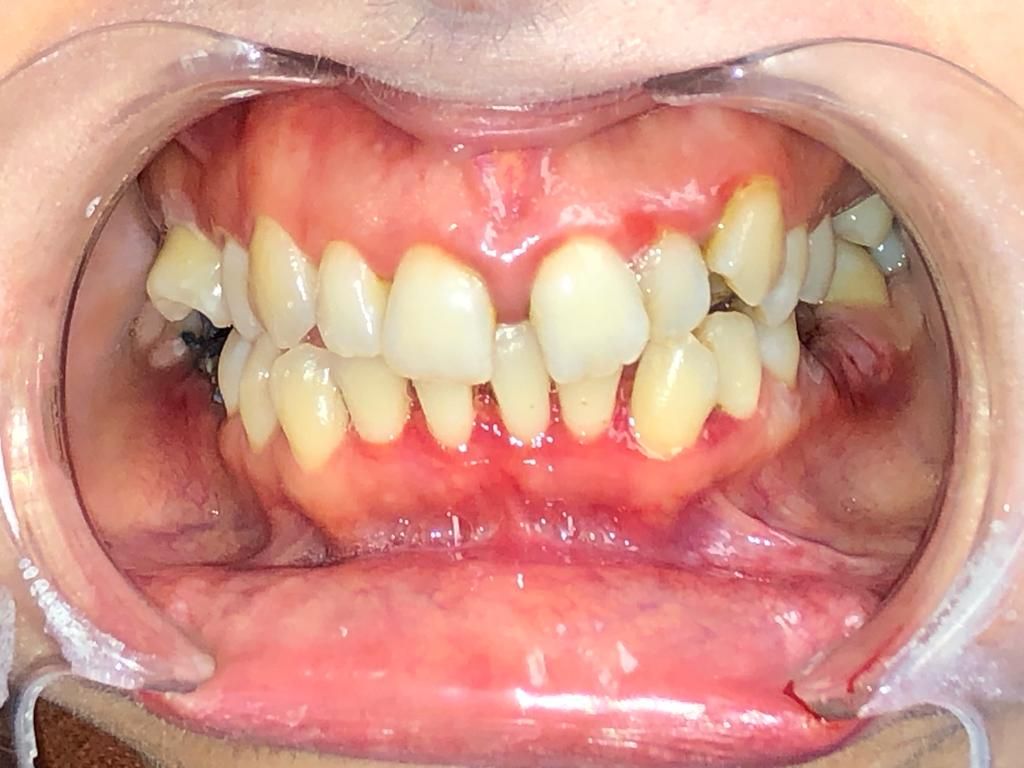

Foto e video

• Parodontologia con il Prof.Sabattini .

Disinfezione delle tasche parodontali, disinfezione di cavità, dei canali radicolari, trattamento dei processi infiammatori, disinfezione e guarigione delle ferite nel post operatorio e post estrattivo, riduzione dell’edema, trattamento di afte orali, lesioni da herpes, candidosi orale, ecc.